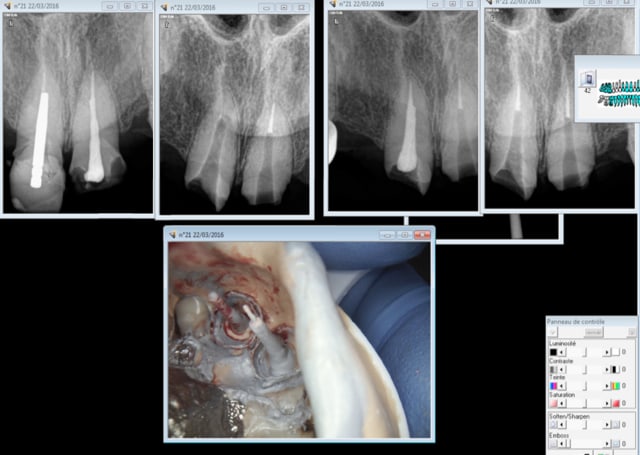

illustration RTE 14 ( arthrite infectieuse pas visible radio) taille empreinte dans la séance ( ic provisoire) 1H.

Capture d e cran 2016 03 15 10.07 - Eugenol